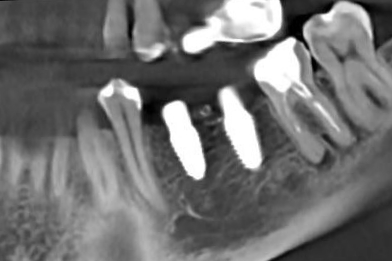

Опыт работы более 3 лет. Внимательный, вежливый доктор, специализируется на хирургической стоматологии. Лечит различные патологии челюсти: кисты, воспалительное заболевания ЧЛХ, удаляет сложные ретинированные зубы мудрости. Осуществляет дентальную имплантации, используя различные методики восстановления костной ткани.

- Имплантация зубов

- Консультация по имплантации зубов

- Одномоментная имплантация зубов

- Дентальная имплантация зубов Osstem

- Дентальная имплантация зубов AnyRidge

- Дентальная имплантация зубов Straumann